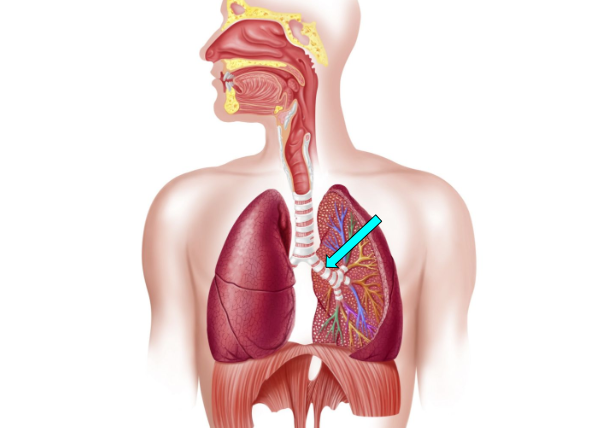

Bronchioles

small airway that delivers oxygen to the alveoli for gas exchange

Bronchi

carry oxygen to and from the lungs

Alveoli

facilitate gas exchange through the lungs & bloods to exchange oxygen & carbon dioxide during respiration

Bronchus (pic)

Bronchioles (pic)

Alveoli (pic)